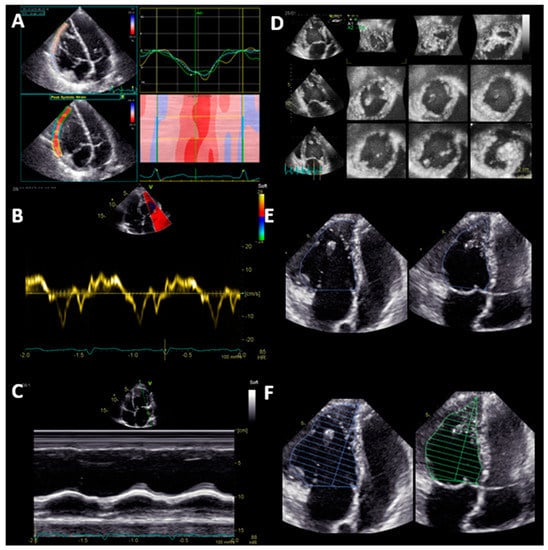

Two different aspects of sysRV function are reported: (1) volumetric function parameters, i.e., 3D end-diastolic volume (EDV), 3D end-systolic volume (ESV), 3D stroke volume (SV), 3D EF, 2D monoplane EF, 2D biplane EF, and FAC; and (2) longitudinal function parameters, i.e., GLS, TAPSE, and S’ (Figure 1).

The basal longitudinal function of the RV can be assessed by tissue Doppler imaging (S’) and by M-Mode. S’ is the peak systolic velocity of the tricuspid annulus measured by tissue Doppler imaging in an apical four-chamber view. For TAPSE, in an apical four-chamber view, the maximal systolic excursion of the lateral tricuspid annulus is measured by M-Mode. GLS of the free lateral wall of the RV was calculated by averaging the peak systolic strain of the three segments of the free lateral wall in an RV-focused four-chamber view. All 3D volumes and EF of the sysRV were analyzed both with TOMTEC 4D RV Function software (TOMTEC Imaging Systems, Munich, Germany) and with GE 4D Auto LVQ software (General Electric Healthcare, Chicago, IL, United States).

Figure 1. Systematic echocardiographic evaluation of systemic right ventricular function: Longitudinal function (Panel A-C) and volumetric function (Panel D-F). (A) Global longitudinal strain of the free lateral wall; (B) tissue Doppler velocity of the basal lateral wall S’; (C) tricuspid annular plane systolic excursion (TAPSE); (D) volumetric function assessed by 3D echocardiography; (E) fractional area change (FAC); (F) monoplane Simpson ejection fraction.